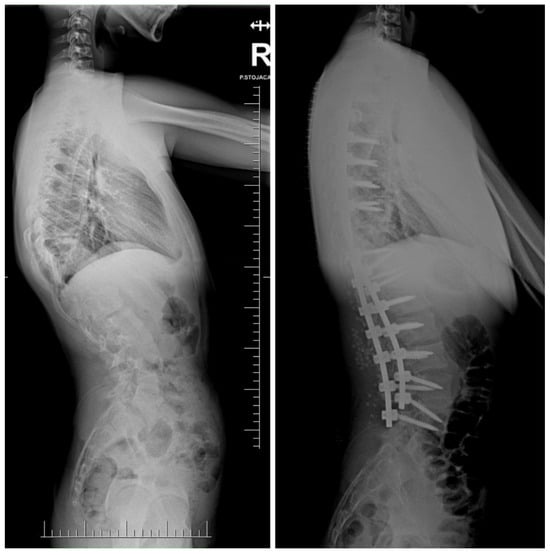

7.3.6. Growth Guidance Systems—Shilla

8. Complications and Risk Management